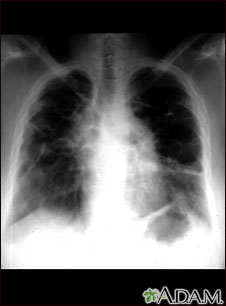

Sarcoid, stage IV - chest x-ray

This film shows advanced sarcoid, scarring of the lungs (the light streaking), and cavity formation (the dark areas in the upper right side of the picture).